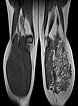

In coronal, non-enhanced T1-weighted control MRI, the vascular component of the lesion is less conspicuous. However, clearly additional soft tissue remains that is pathologic (“salt-and-pepper pattern”). This tissue consists in part of hyperintense adipose tissue and in part of hypointense connective tissue. This is the typical MRI appearance of a fibro-adipose vascular anomaly (FAVA).

The vascular channels are largely occluded on axial control MRI in T2-weighted images. However, after successful occlusion of the vascular channels, a black-and-white “salt-and-pepper” pattern typical of FAVA remains. This consists of adipose tissue (hyperintense) and connective tissue (hypointense).